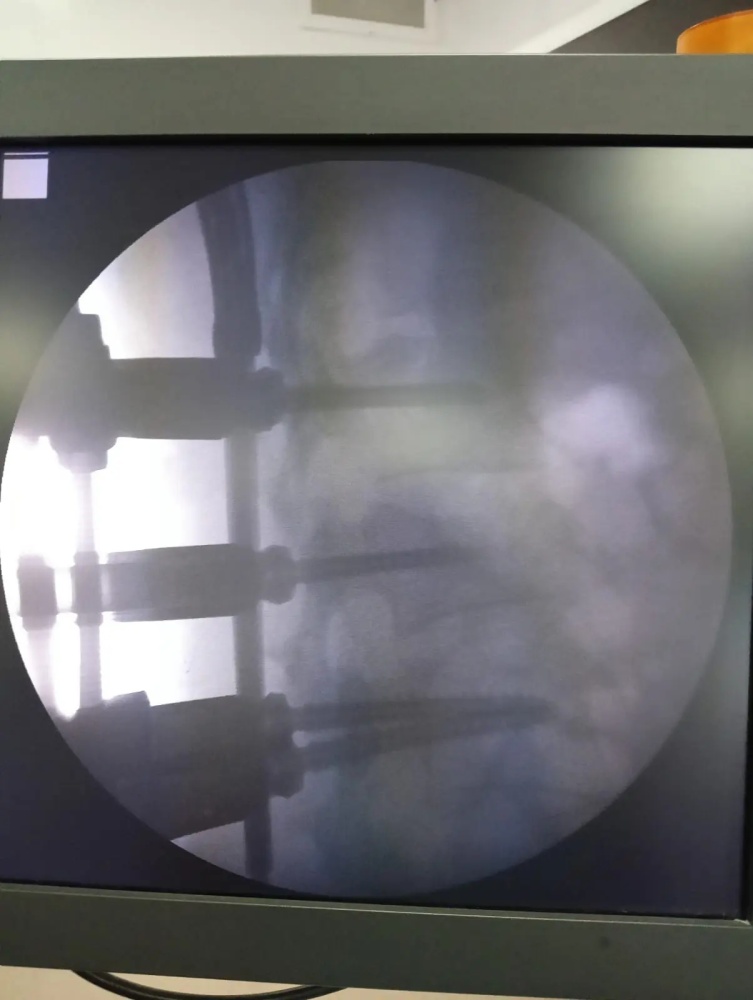

Диагноз - Острая позвоночно-спинномозговая травма, нестабильный компрессионно-оскольчатый перелом тела 2-го поясничного позвонка.

Под контролем лучевой навигации через мини-разрезы (по 2 см) с использованием специальных портов были установлены транспедикулярные винты и штанги.

- восстановлена высота сломанного позвонка,

- зафиксирован повреждённый сегмент,

- осколок успешно импактирован винтом.